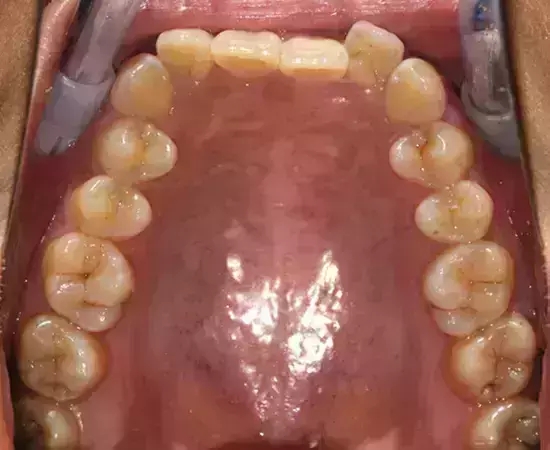

Damon 病例分享:安氏 II 類二分類露齦笑的矯治(董一磊)

治療前后對比